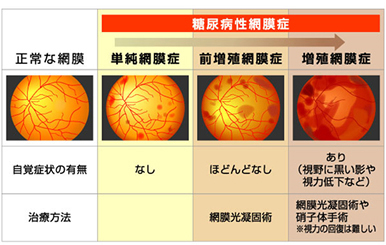

糖尿病網膜症

糖尿病網膜症とは、糖尿病の三大合併症の一つであり、日本の中途失明原因の上位となっています。

糖尿病網膜症は、糖尿病が原因で目の中の網膜という組織が障害を受け、視力が低下する病気です。

| 主な症状 |

初期(単純網膜症) まだ自覚症状がみられません。しかし、目の中の血管の状態をみると、小さな出血など、少しずつ異常があらわれています。 中期(前増殖網膜症) 視界がかすむなどの症状が感じられます。

末期(増殖網膜症) 視力低下や飛蚊症が起こり、さらには失明に至ることもあります。 |

|---|---|

| 検査 |

糖尿病の方は少なくとも半年に1回の診察をお勧めしています。 |

| 主な治療法 |

|